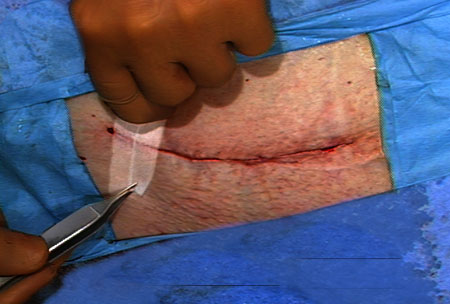

Running, or Continuous Stitch

The "Running" stitch is made with one continuous length of suture material. Used to close tissue layers which require close approximation, such as the peritoneum. May also be used in skin or blood vessels. The advantages of the running stitch are speed of execution, and accommodation of edema during the wound healing process. However, there is a greater potential for malapproximation of wound edges with the running stitch than with the interrupted stitch